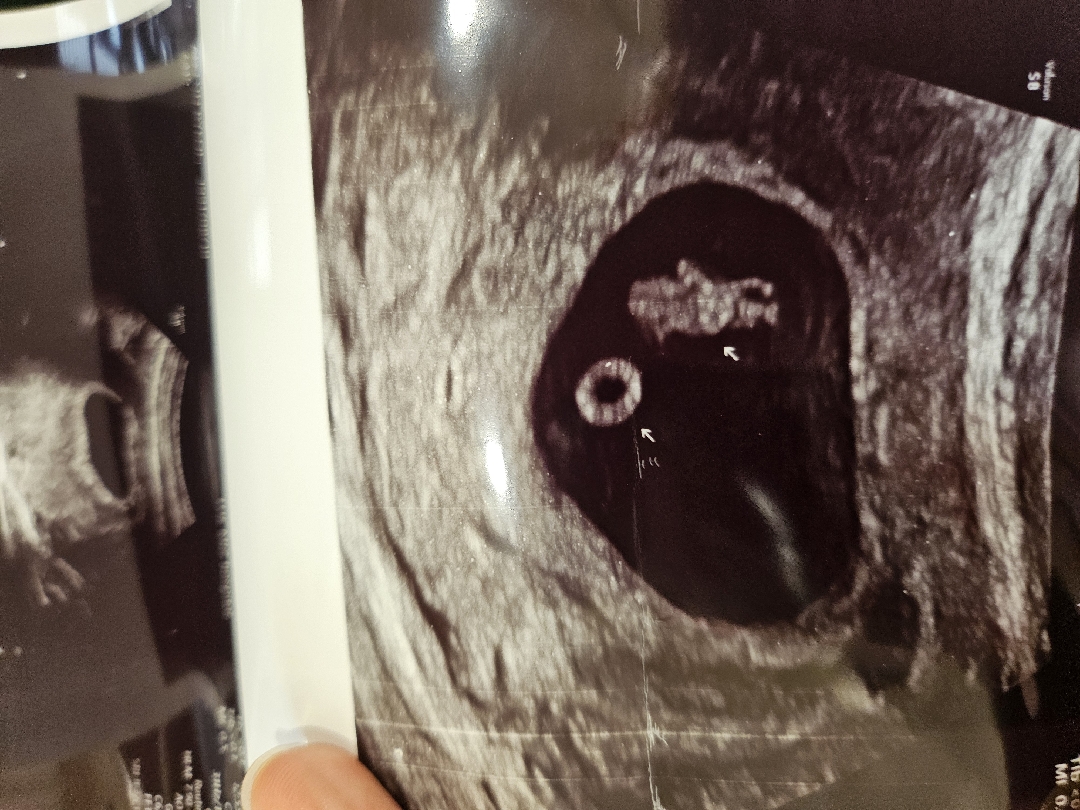

귀여운 미니콩이 만세 하고있네요!! 첫째때는 뭐가 머리이고 팔다리인지 봐도 잘 모르겠더니 둘째는 남편한테 초음파 사진 보내주니까 바로 만세하고있네~ 하더라고요 경력직 둘째 아빠는 다르네요 ㅋㅋ

와 난황이랑 아기모습이 정말 또렷하네요! 신기하고 귀여워요ㅎㅎ

너무 귀엽고 신기하네요😍😍 초음파에서 이정도로 보일려면 몇주쯤 될까용??? 저는 이제 7주 조금 넘은 예비맘이에용~ ㅎㅎ